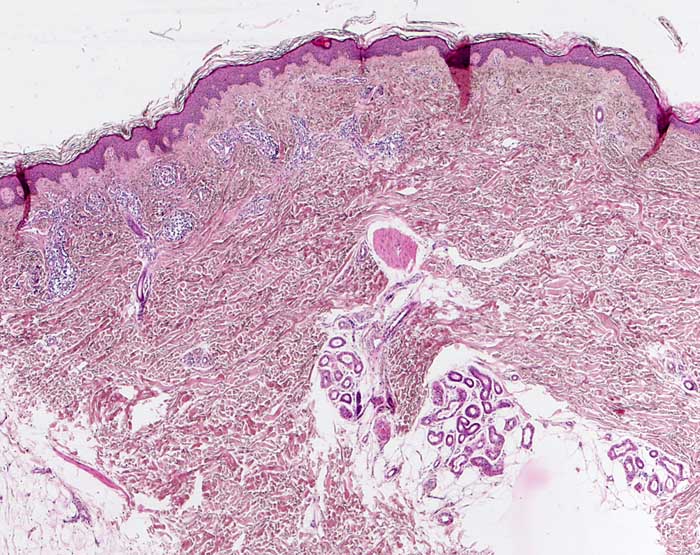

normale Felderhaut vom Oberschenkel

Haut, untere Extremität

Das Korium der Oberschenkelhaut ist etwas dünner als das Korium der Rückenhaut. Haare sind nicht sehr zahlreich und reichen nicht sehr tief. In diesem Anschnitt ist lediglich ein Musculus arrector pili sichtbar, der auf die Anwesenheit eines Haarfollikels hindeutet.

25